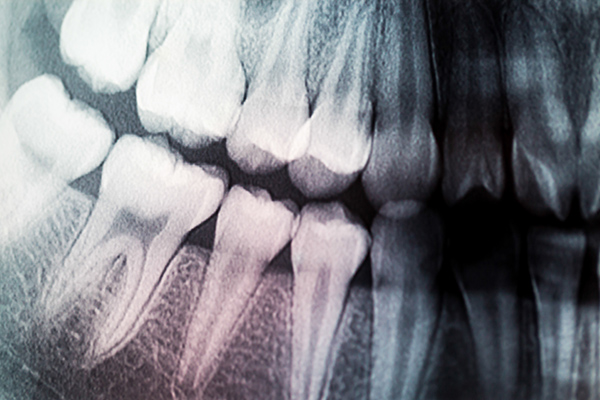

General dentistry care can offer many benefits for your oral health. Dental X-rays are an important diagnostic tool that can reveal problems not visible to the naked eye, including cavities between teeth, bone loss due to gum disease, abscesses, tumors, cysts, and impacted teeth. Different types of X-rays include bitewing X-rays, periapical X-rays, and panoramic X-rays. X-rays are safe and use very low levels of radiation. Your dentist uses this information to develop a complete treatment plan for your oral health.